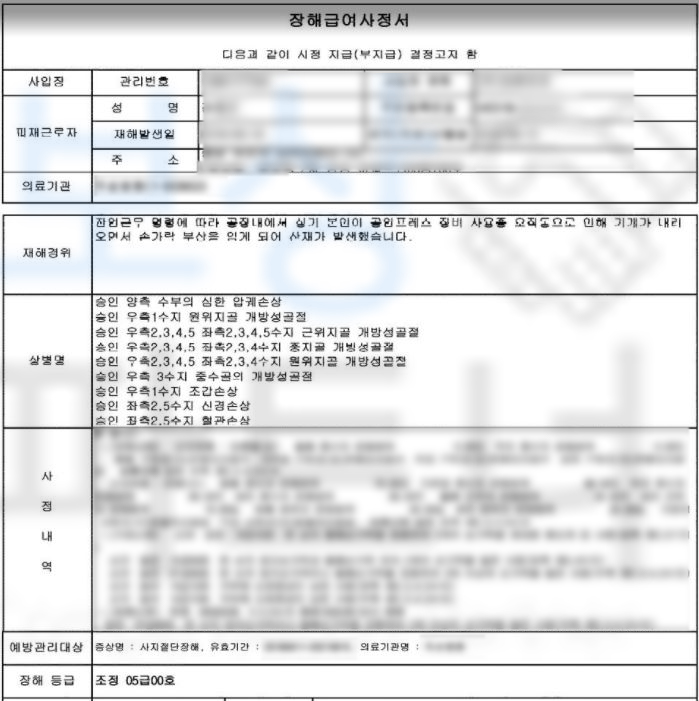

**산재장해등급 5급 **인정받아

장해급여 연금으로 12,108,048원

지급받을 수 있었습니다. 산재장해등급은 다치고 수술했다고 해서 무조건 해당되는 것이 아닌 산재 장해판정 기준에 부합해야 지급되는 보험급여입니다. 강@@님의 상황을 보면 으깸손상 (압궤손상) s678 진단받아 무조건적으로 해당되어 보였지만

각 손가락마다 정확하고 적정한

산재장해등급 결정을 위해서는

산재 약관을 잘 알고 있는

보상 파트너의 도움이 필요하였습니다.

보상 파트너는 강@@님의 요양 기간 동안 의뢰인의 장해의 정도를 검토하고 미리 서류를 준비하였습니다. 요양 종결 시점 산재 장해급여 청구 시 종경 병원의 주치의와 함께 면담을 진행하여 객관적이면서 정확하게 장해판정이 이루어지도록 이끌었고 관할 공단의 장해판정까지 함께 주의 깊이 진행한 결과

산재 장해등급 5급

이끌어낼 수 있었죠.